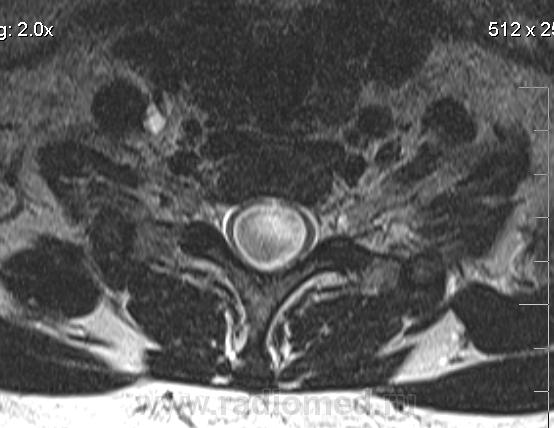

Убедительных данных за патологическое накопление контрастного препарата не выявлено. Кисты с повышенным содержанием белка (?), может быть бывают атеромы в области мягких тканей шеи (гиперинтенсивные по Т1 между мышцами шеи справа)?

Cпасибо большое, как вы думаете, это  кисты в области мягких тканей шеи справа (гиперинтеснивные по Т1 и Т2), или что-то другое?

морфологически- явно кистозные образования. А вот их происхождение - вопрос.